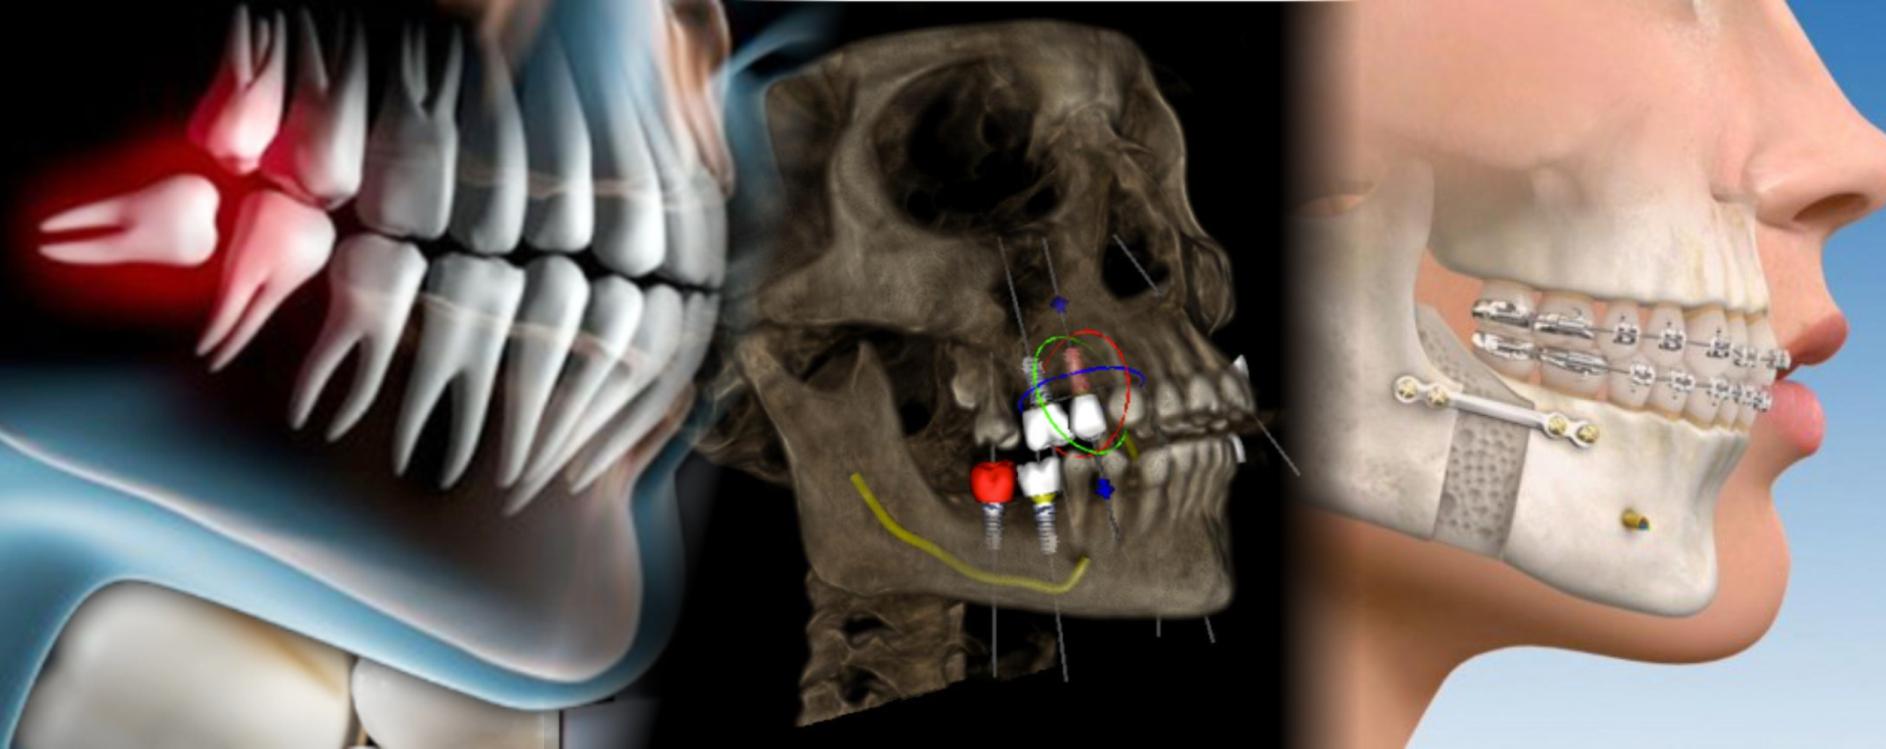

Cirugía Oral y Maxilofacial

Implantes Dentales

Ced. Espec. 7130382 UNAM

Horario:

Lunes a Viernes:

9:00 am a 1:00 pm y 4:00 pm a 8:00 pm

Sábados: 9:00 am a 1:00 pm

Trauma facial

Corrección de Maxilares

(cirugía ortognática)

Cirugía terceros molares

Patologías de maxilares